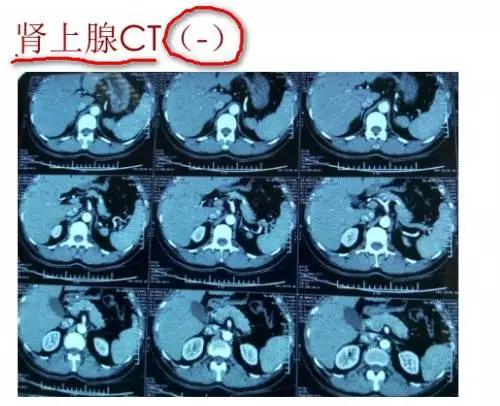

为了进一步排除内分泌性高血压,我们做了醛固酮卧立位试验、甲功、24h尿儿茶酚胺、血总皮质醇、肾上腺CT检查。

③肾上腺CT:无肾上腺增粗或者肾上腺瘤表现。